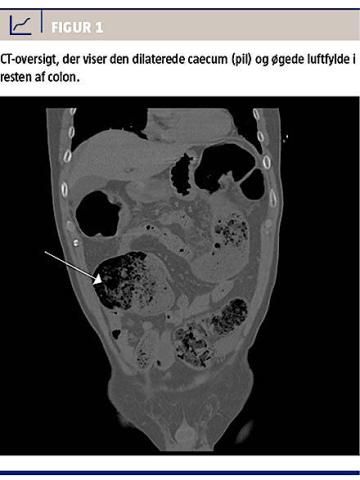

En CT-tomskanning viste distal koprostase med tegn på colon ileus og dilateret tarm fra colon descendens til caecum (Figur 1).